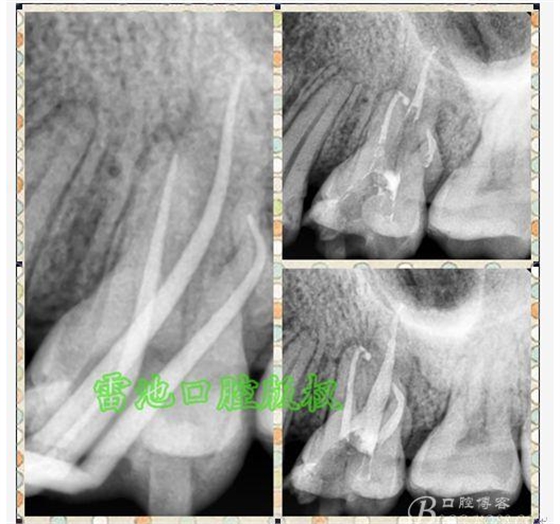

E、X線影像學的檢查研判能力:這點不需要強調(diào)太多,對于普通的非CBCT的二維影像對醫(yī)生讀片能力有一定的要求,有個逐步提高的過程,非一蹴而就,需要學會把二維的X線影像與三維的解剖結(jié)構(gòu)進行良好的對應結(jié)合,對于某些鈣化的髓室底,應通過想象把根管口的分布、根管的走向以及各種變化通過想象投射到對應的髓室底上;

G:找尋MB2的問題:

1、查閱各種文獻,MB2的發(fā)生率在52-96%之間,治療時遺漏是上頜磨牙根管治療失敗的主因,2、一般位于MB1根管口與腭根管口方向的0.5-5mm范圍內(nèi),而大多數(shù)都位于MB舌側(cè)的1-3mm處,其中2mm以內(nèi)占85.7%,3、MB1-P根管口連線與MB1-MB2根管口的連線夾角大部分(74.3%)在30度以內(nèi);4、MB2的尋找大部分需要去除相應部位的牙本質(zhì);5、當找到的MB根管口呈“長線型”且有深色凹線向舌側(cè),或者找到的MB根管口明顯偏頰多提示有MB2的可能;6、DOM(牙科手術(shù)顯微鏡)的使用有助于找尋MB2;